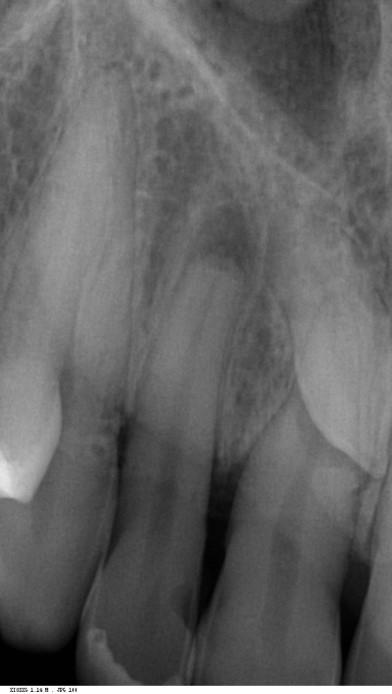

A hagyományos endodontiai kezelés különböző fázisokon alapul, amelyek a pulpa és a periapikális terület akut vagy krónikus gyulladásának megszüntetését eredményezik (1. táblázat) [1-3]. A terápia különböző fázisai a következők:

1. táblázat: Az endodontiai patológia diagnosztikai osztályozása [1-3].

A tisztítási és alakítási fázisok két különböző típusú tisztítást foglalnak magukban: a kémiai tisztítást, amelyet különböző öblítőoldatokkal végeznek, és a mechanikai tisztítást, amelyet a gyökércsatornákat alakító endodontiai eszközökkel végeznek. Számos tanulmány azonban kimutatta a vizsgált műszerek nem teljes hatását, amelyek a csatorna felszínének 35%-át vagy annál nagyobb részét változatlanul hagyták [4-6]. Ennek megfelelően az endodontikus tér hatékony átmosása határozza meg a terápia sikerét. A formázási fázisban a kézi irrigálást vég- vagy oldalnyílású tűvel ellátott fecskendővel végezzük, váltakozva a különböző méretű reszelőket használó műszeres kezeléssel. A baktériumterhelés csökkentése mellett az irrigálószerek a végső aktivált irrigációs protokollt megelőző reszelés során kenőanyagként is működnek. E cikk célja, hogy bemutassa az endodontiai terápia innovatív logikáját a legújabb, legmodernebb SWEEPS (shock wave enhanced emission photoacoustic streaming) lézertechnológia alkalmazásával.

Lézerrel aktivált öntözés a SWEEPS segítségével

A lézeraktivált öntözés és a SWEEPS-technológia fizikai koncepcióit már ismertettük e magazin egy korábbi számában (4/2019) [18]. A SWEEPS egyik nagy előnye az összes többi aktiválási technikával szemben a mélyreható hatékonysága. Az összes többi technikával ellentétben a SWEEPS hatása nem korlátozódik a hegy környékére, mint az ultrahangos irrigálás esetében, hanem a gyökércsatorna-rendszer távolabbi régióiban is hatékony [19, 20]. Ezért a SWEEPS-nek csak a hegynek a hozzáférési üregben való elhelyezésére van szüksége ahhoz, hogy az irrigálószer egyszerre áramoljon az egész endodontikus térbe. Ez eltér más technikáktól, amelyeknél a gyökércsatornák előkészítése után tűt vagy hegyet/reszelőt vagy szondát kell bevezetni az egyes csatornák apikális harmadáig vagy annál tovább az irrigáláshoz. Így a SWEEPS a terápia kezdeti fázisától egészen a végső fázisig használható, lehetővé téve a baktériumterhelés fokozatos csökkentését, mielőtt bármilyen reszelőt használnának. A SWEEPS hatékonysága és eredményessége az endodontikus oldatok kémiai aktiválásán alapul az agitáció révén, [21, 22] ami javítja az irrigánsok baktériumölő és szövetoldó képességét, valamint a gyökércsatorna falának tisztítását szolgáló mechanikus öblítőhatáson [23, 24].

A kutatók a SWEEPS kettős modalitást hatékonyabbnak találták, mint az egy impulzusos SSP (super-short pulse; PIPS, photon-induced photoacoustic streaming) modalitást [2528]. A SWEEPS kettős impulzusos modalitást alkalmazva a második lézerimpulzus által generált második buborék hirtelen tágulása további nyomást gyakorol az első buborékra, ami annak heves összeomlásához vezet, amelynek során lökéshullámok keletkeznek a nagyon kis csatornákban is. Továbbá lökéshullámokat bocsátanak ki az összeomló másodlagos kavitációs buborékok, amelyek a lézerrel aktivált irrigálás során a csatorna teljes hosszában természetes módon

1. ábra: A 12. fog - a röntgenfelvételen nagyméretű periapikális elváltozás látható. A tünetmentes fogat ISO 25/.06 TF Adaptive reszelővel (Kerr Dental) preparáltuk. – 2. ábra: A 12. fog gyökércsatornájának tömését ásványi trioxid aggregátummal (ENDOSEAL MTA, Maruchi) végeztük. Figyeljük meg az apikális elágazás lezárását, ami az apikális terminus hatékony tisztítása és dekontaminálása miatt lehetséges. A gyógyulás 12 hónap elteltével csaknem teljes volt. – 3. ábra: 33. fog - a páciensnél egy bukkális sinus traktus volt látható, amely röntgenfelvételen a 32. és a 33. fog közötti területnek felelt meg. A CBCT és a röntgenfelvétel nagyméretű periradikuláris elváltozást mutatott, különösen a disztális oldalon. A preparálást 20/,07v ProTaper Gold (F1; Dentsply Sirona) készülékkel végeztük. – 4. ábra: A 33. fog gyökércsatorna obturációját sealer és hordozó alapú guttapercha (AH Plus és Thermafil, Dentsply Sirona) segítségével végeztük. A hat hónappal a műtét után végzett röntgenellenőrzés azt mutatta, hogy több oldalsó csatorna feltöltődött, és a gyógyulási folyamat folyamatban van.

keletkeznek [25-29]. A másodlagos kavitációs buborékok összeomlásuk során a csatornafalak közvetlen közelében vannak, nyírófeszültséget és örvényes áramlásokat generálva, amelyek képesek eltávolítani a törmeléket, a kenetréteget és a biofilmet a gyökércsatorna felszínéről, valamint a fel nem fedezett és műszerrel nem rendelkező anatómiai területekről, például az isztmuszokból, az oldalsó csatornákból, a hurkokból és a ramifikációkból, ezáltal tovább fokozva a tisztítási és dekontaminációs mechanizmust (1-4. ábra). A gyökércsatorna mentén létrejövő fokozott nyomás következésképpen az irrigálószereknek a dentinális tubulusokba való behatolásának mélységét is növeli [25-28].

Klinikai protokollok

Ezen a ponton a hozzáférési üreget egy kis keményfém, vagy hengeres vagy kerek gyémántfúró segítségével nagyítás mellett (4,5-6,0 x) megnyitjuk. A hagyományos hozzáférési üreg előkészítése a centralitás és koncentricitás törvényeit követve célszerű (5. ábra) [30]. Több tanulmány is bizonyította, hogy az ultrakonzervatív „ninja” hozzáférési üreg előkészítése nem hasznos a törésszilárdság és az eredeti csatorna anatómia megőrzése szempontjából a formázás során a hagyományos hozzáférési üreg előkészítéséhez képest, különösen az apikális szinten. Továbbá, a standardizált hozzáférési üreg előkészítése tanácsos, ha az X-SWEEPS modalitást választjuk a lézerrel aktivált irrigáláshoz. A jövőbeni publikációkban ezt a témát részletesen ki fogjuk fejteni, hogy megállapíthassuk a standardizált hozzáférési üreg-előkészítési térfogat mellett alkalmazandó helyes lézerbeállításokat. Bármilyen patológiáról legyen is szó, a koncepció a gyökércsatorna alakításának minimalizálása, az endodontikus tér tisztításának és dekontaminációjának optimalizálása a SWEEPS kemo-mechanikus öblítésének kihasználásával. A fő különbség a tünetmentes és a tüneti pulpitisz és az apikális parodontitis terápiája között a hosszabb vagy rövidebb NaOCl SWEEPS-aktivált kezdeti öblítési fázisban van. A retreatment szintén tartalmaz néhány különbséget a kezdeti

Tünetmentes és tünetmentes irreverzibilis pulpitis

Irreverzibilis pulpitisz esetén a pulpa visszafordíthatatlanul gyulladt, akut tünetekkel vagy anélkül. A páciens életkora és a műtét előtti röntgenfelvétel információt ad egy esetleges éretlen csúcsról; ez az állapot ellenjavallt a teljes erejű SWEEPS-öblítésre, és óvatosabb beavatkozást és az alkalmazott energia csökkentését javasolja (erről bővebben később). A pulpakamra megnyitása után túlzott vérzés jelentkezhet, ami gyulladt pulpaszövet jelenlétére utal a kamrában és a gyökércsatornákban. Ebben az esetben egy látogatásos kezelés javasolt. A kezelés NaOCl-öblítéssel kezdődik fecskendővel (3-5 ml) és egyidejű aktiválással Er:YAG lézerrel (2940 nm; LightWalker AT, Fotona), a kétimpulzusos (25 μs du-ration) Auto-SWEEPS modalitással 30-40 másodpercig. Az irrigálást követő nyugalmi idő 1-2 percre meghosszabbítható, hogy a NaOCl-pulpa nagyobb mértékű feloldódását tegye lehetővé. Lapos vagy radiális végű SWEEPS hegyet (400 μ) használunk. A pulpaszövetben a gyulladás különböző fokozatait (szintjeit) lehet kimutatni, egészen a kezdeti nekrotikus degenerációig. Ebben a szakaszban fontos mérlegelni, hogy maga a pulpaszövet megakadályozza-e az irrigálószer extrudálását, így a teljes teljesítményű Auto-SWEEPS aktiválás (20 mJ 15 Hz-en és 0,6 W-on) elvégezhető a pulpa majdnem teljes feloldódásáig, amit a vérzés fokozatos csökkenése jelez. A fog típusától és állapotától függően ez a kezdeti fázis egygyökerű fogak esetében két-három, premolárisok és molárisok esetében pedig akár három-négy cikluson keresztül is megismételhető.